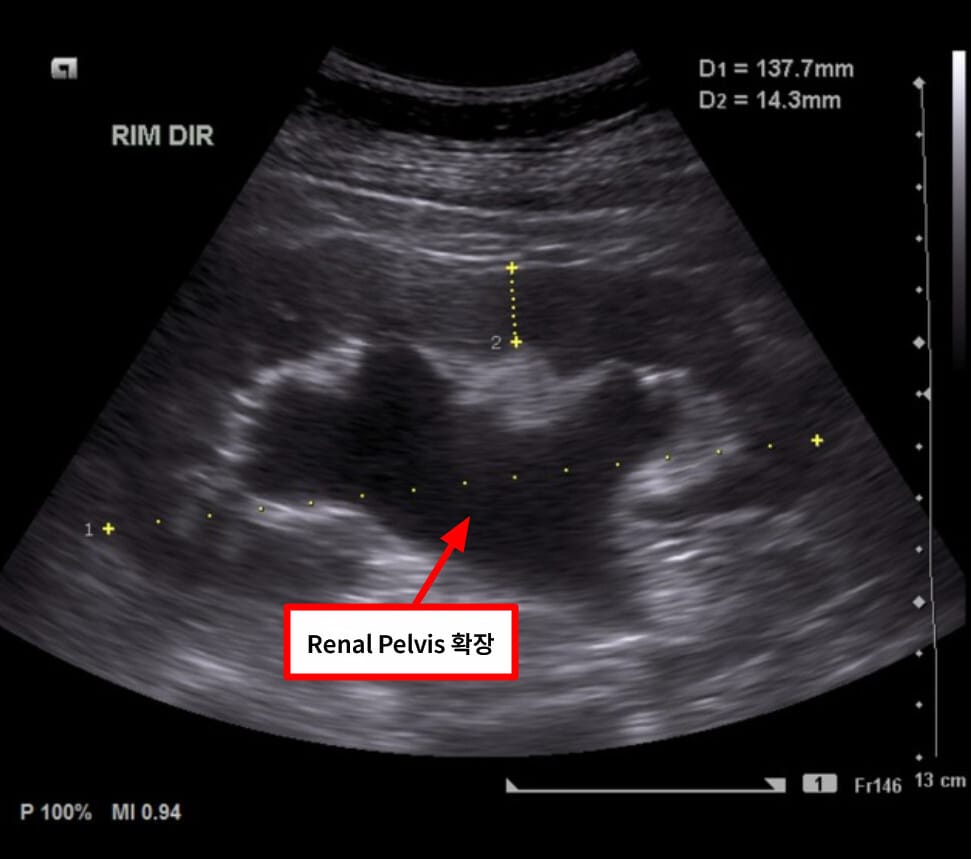

| 🔵 신장 초음파 |

| 가장 흔히 사용되며, 신우 확장 확인에 민감합니다. 방사선 노출이 없고 간편합니다. |

수신증의 영상은 확장된 신우/신배 및 폐쇄 위치 확인.

| 🔍 특징적 영상소견 요약 |

| ✅ 신우 및 신배의 확장 |

| 초음파 또는 CT에서 신장 내부가 검고 넓게 확장되어 보입니다. |